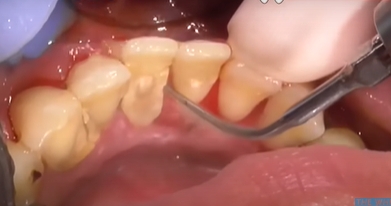

치석 떨어짐 구멍 채우는 방법

첫 번째로 플러그 또는 레진으로 채우는 방법입니다. 구멍이 작지만 음식물이 자주 끼거나 시린 증상이 심한 경우에는 치아색의 레진으로 메워주는 방법을 씁니다. 심미적으로도 깔끔하고 시림 현상을 줄이는 데 도움이 됩니다.

두 번째로 잇몸이 많이 내려가서 생긴 구멍이라면 스케일링 후 치주 치료를 통해 잇몸 회복을 유도하거나 잇몸이식을 진행하기도 합니다.